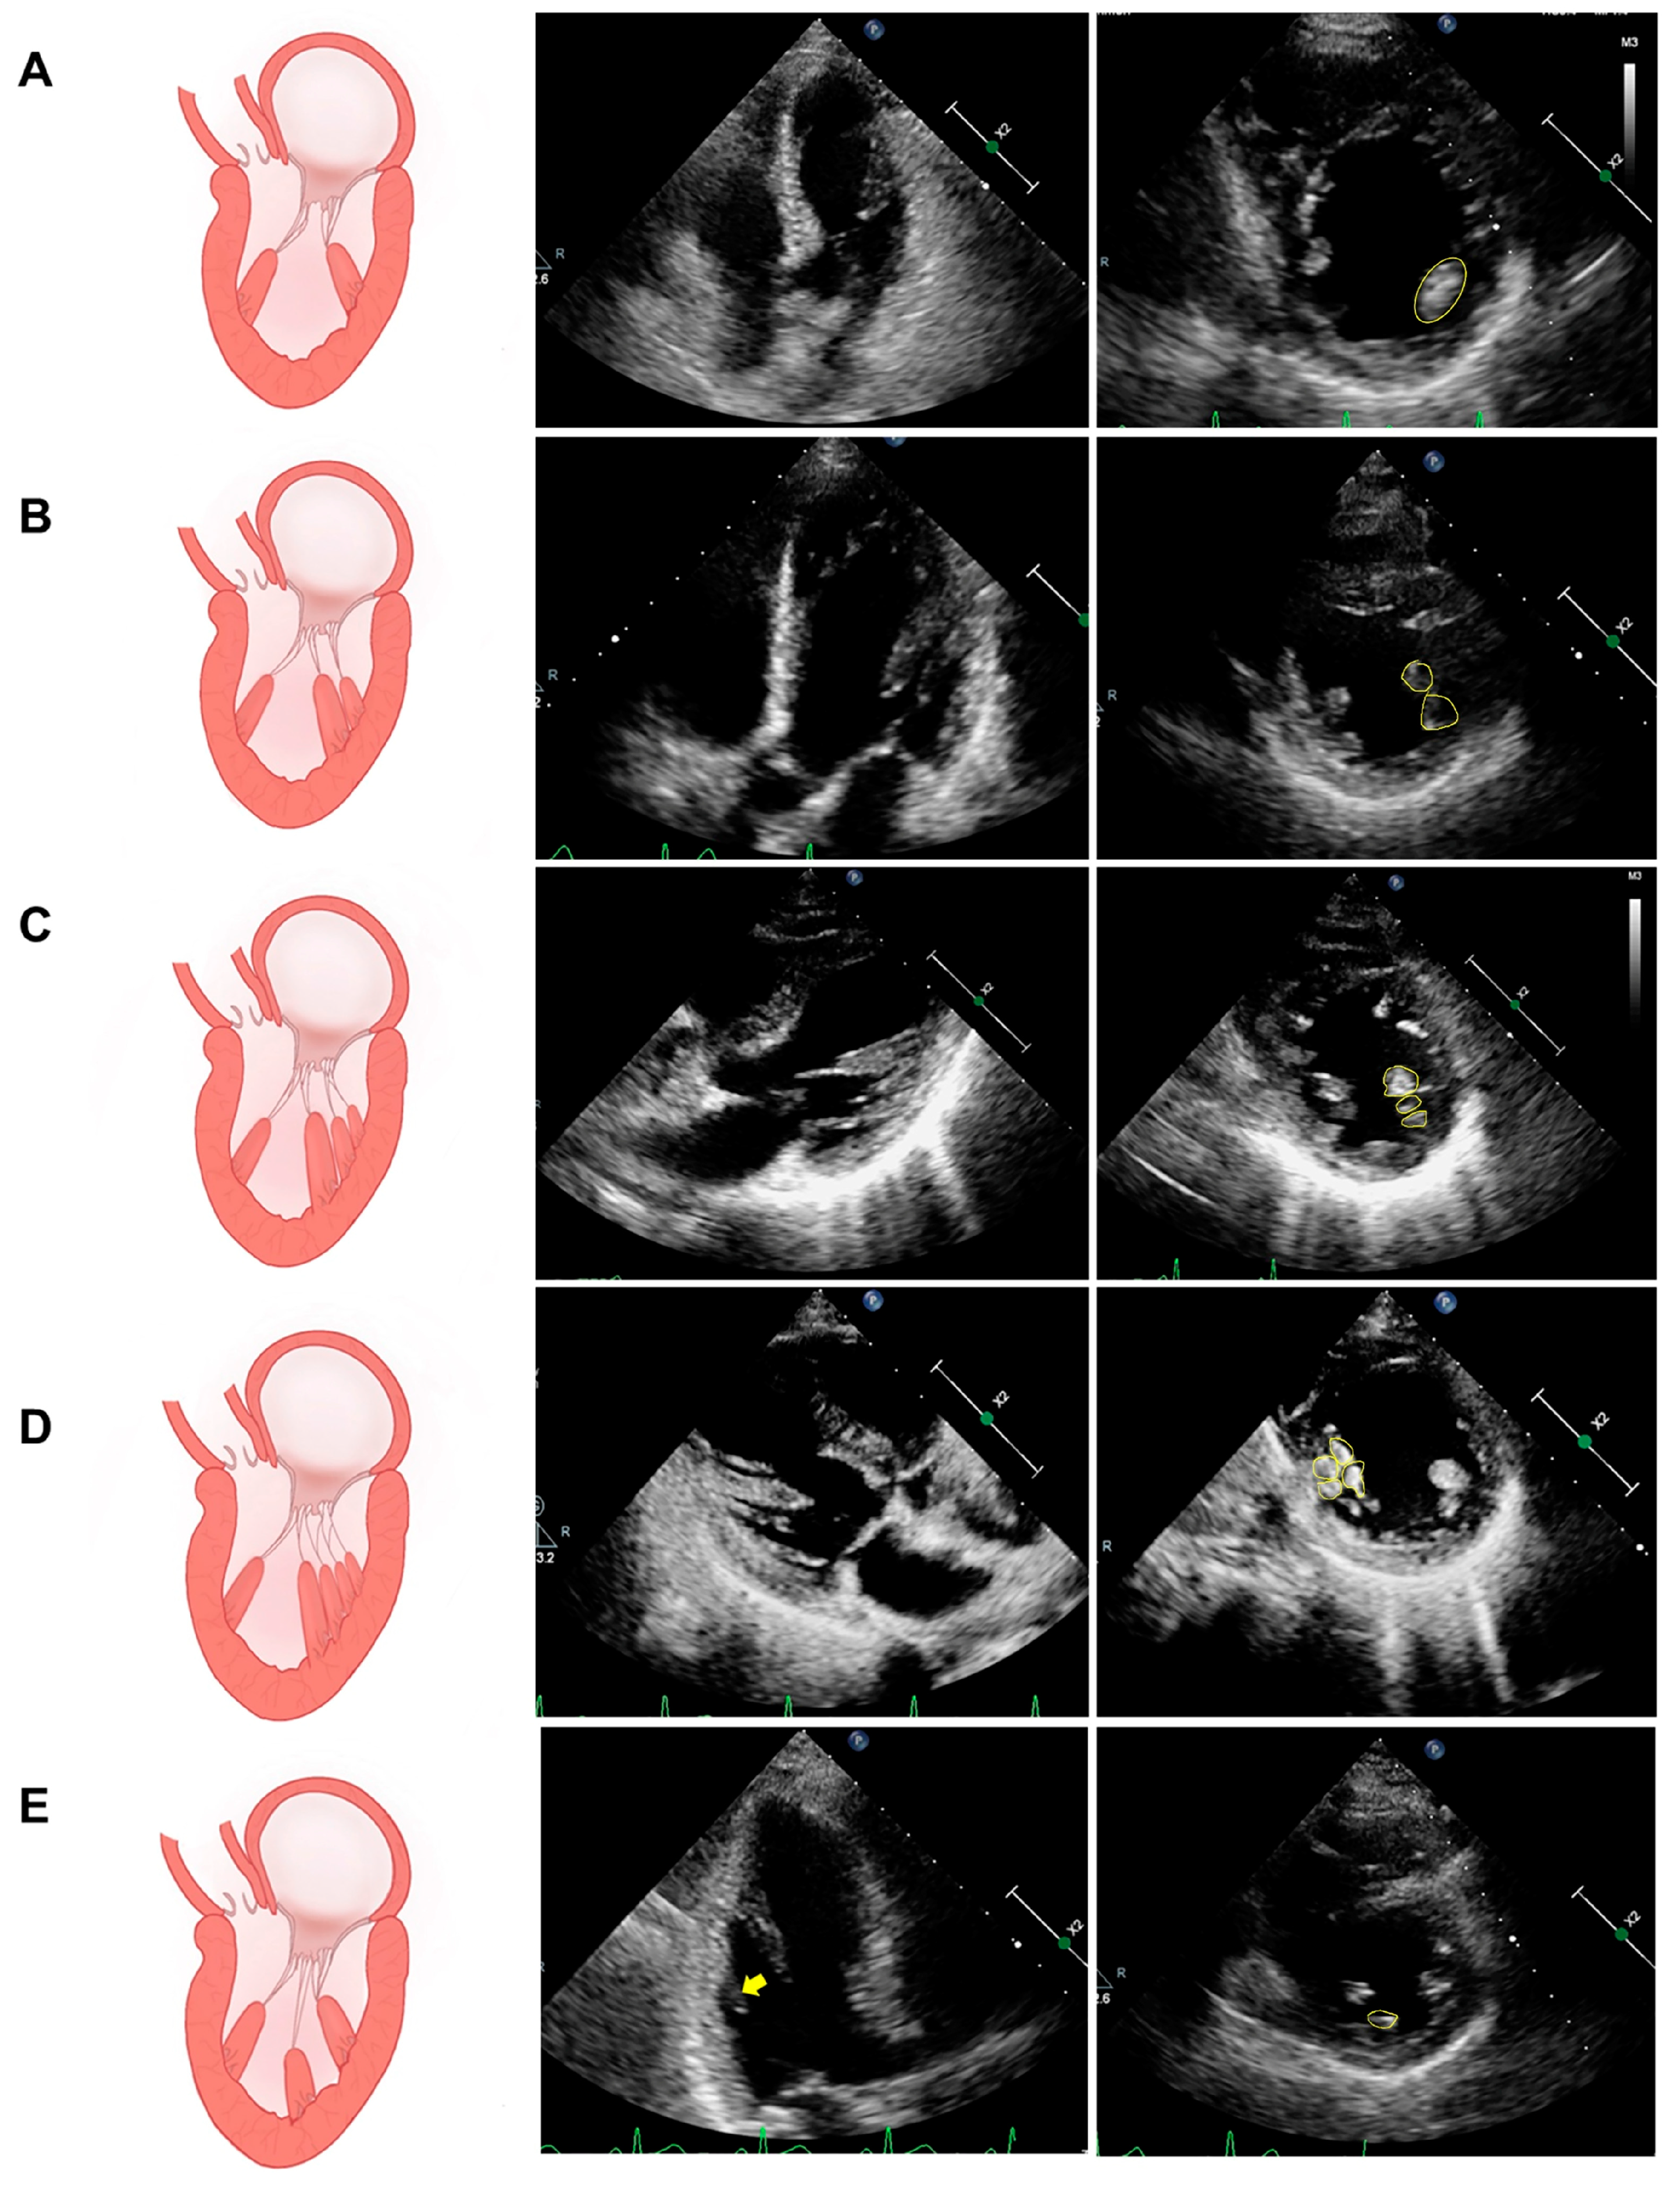

2.1. PM Structure and Variation

5.1. Assessment of PM Structure